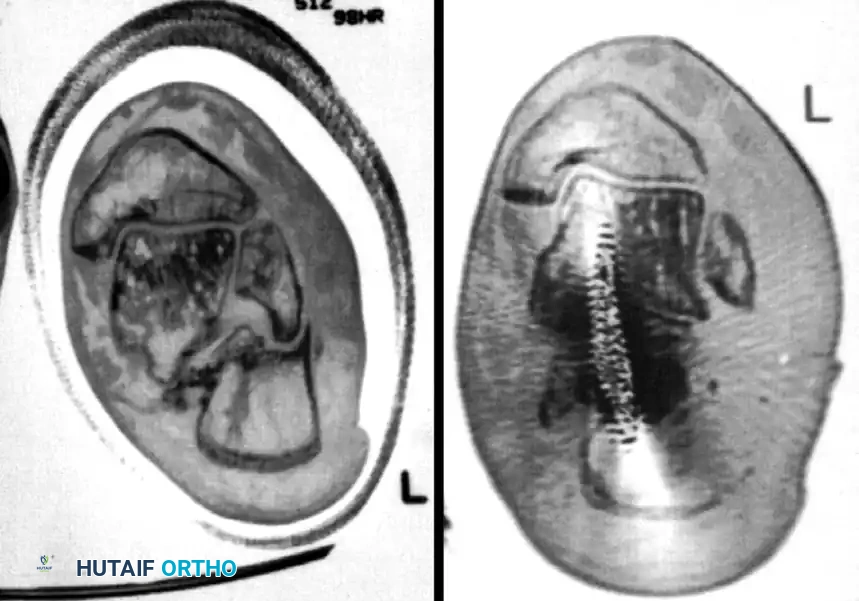

Meticulous preoperative planning is essential for successful percutaneous fixation. Standard radiographs, including lateral, axial (Harris), and anteroposterior views of the foot, should be obtained. A fine-cut computed tomography (CT) scan with sagittal and coronal reconstructions is mandatory to delineate the fracture pattern, assess the degree of posterior facet comminution, and classify the injury according to the Sanders classification system. Percutaneous techniques are most amenable to Sanders Type IIA and IIB fractures, where the posterior facet is split into two primary articular fragments.

Definitive stabilization is achieved using cannulated screws, which provide compression across the fracture lines and rigid maintenance of the restored anatomy.

- Place 3.5-mm or 4.0-mm partially threaded cortical screws over the provisional K-wires. These screws are directed from lateral to medial, compressing the lateral articular fragment against the medial sustentacular fragment.

- To maintain the corrected position of the tuberosity, insert fully threaded screws from the posterior tuberosity directed anteriorly toward the calcaneocuboid joint, parallel to the initial Steinmann pin. Fully threaded screws are preferred here to act as position screws, preventing loss of calcaneal length.

- Perform a final fluoroscopic check to confirm extra-articular hardware placement, restoration of Böhler’s angle, and correction of varus alignment.